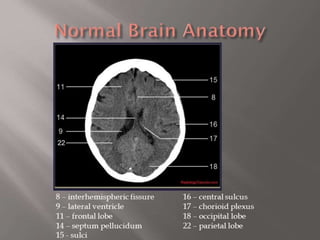

Fig 2a: T1 MRI axial projection. 1: inter-

hemispheric scissure; 2: lateral sulcus; 3:

frontal lobe; 4: insula lobe; 5: temporal lobe; 6:

occipital lobe.

Fig 2a: T1MRI axial projection. 1: inter- hemispheric scissure; 2: lateral sulcus; 3: frontal lobe; 4: insula lobe; 5: temporal lobe; 6: occipital lobe.